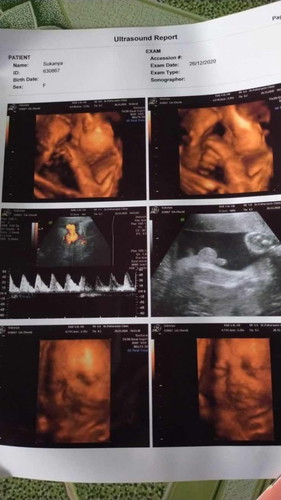

29wแล้วครับ ลุงหมอบอกมีสายรกพันคอ1รอบแม่นี้กังวลมาเลยค่ะ

อย่ากังวลค่ะแม่ พัน3รอบถึงจะอันตราย